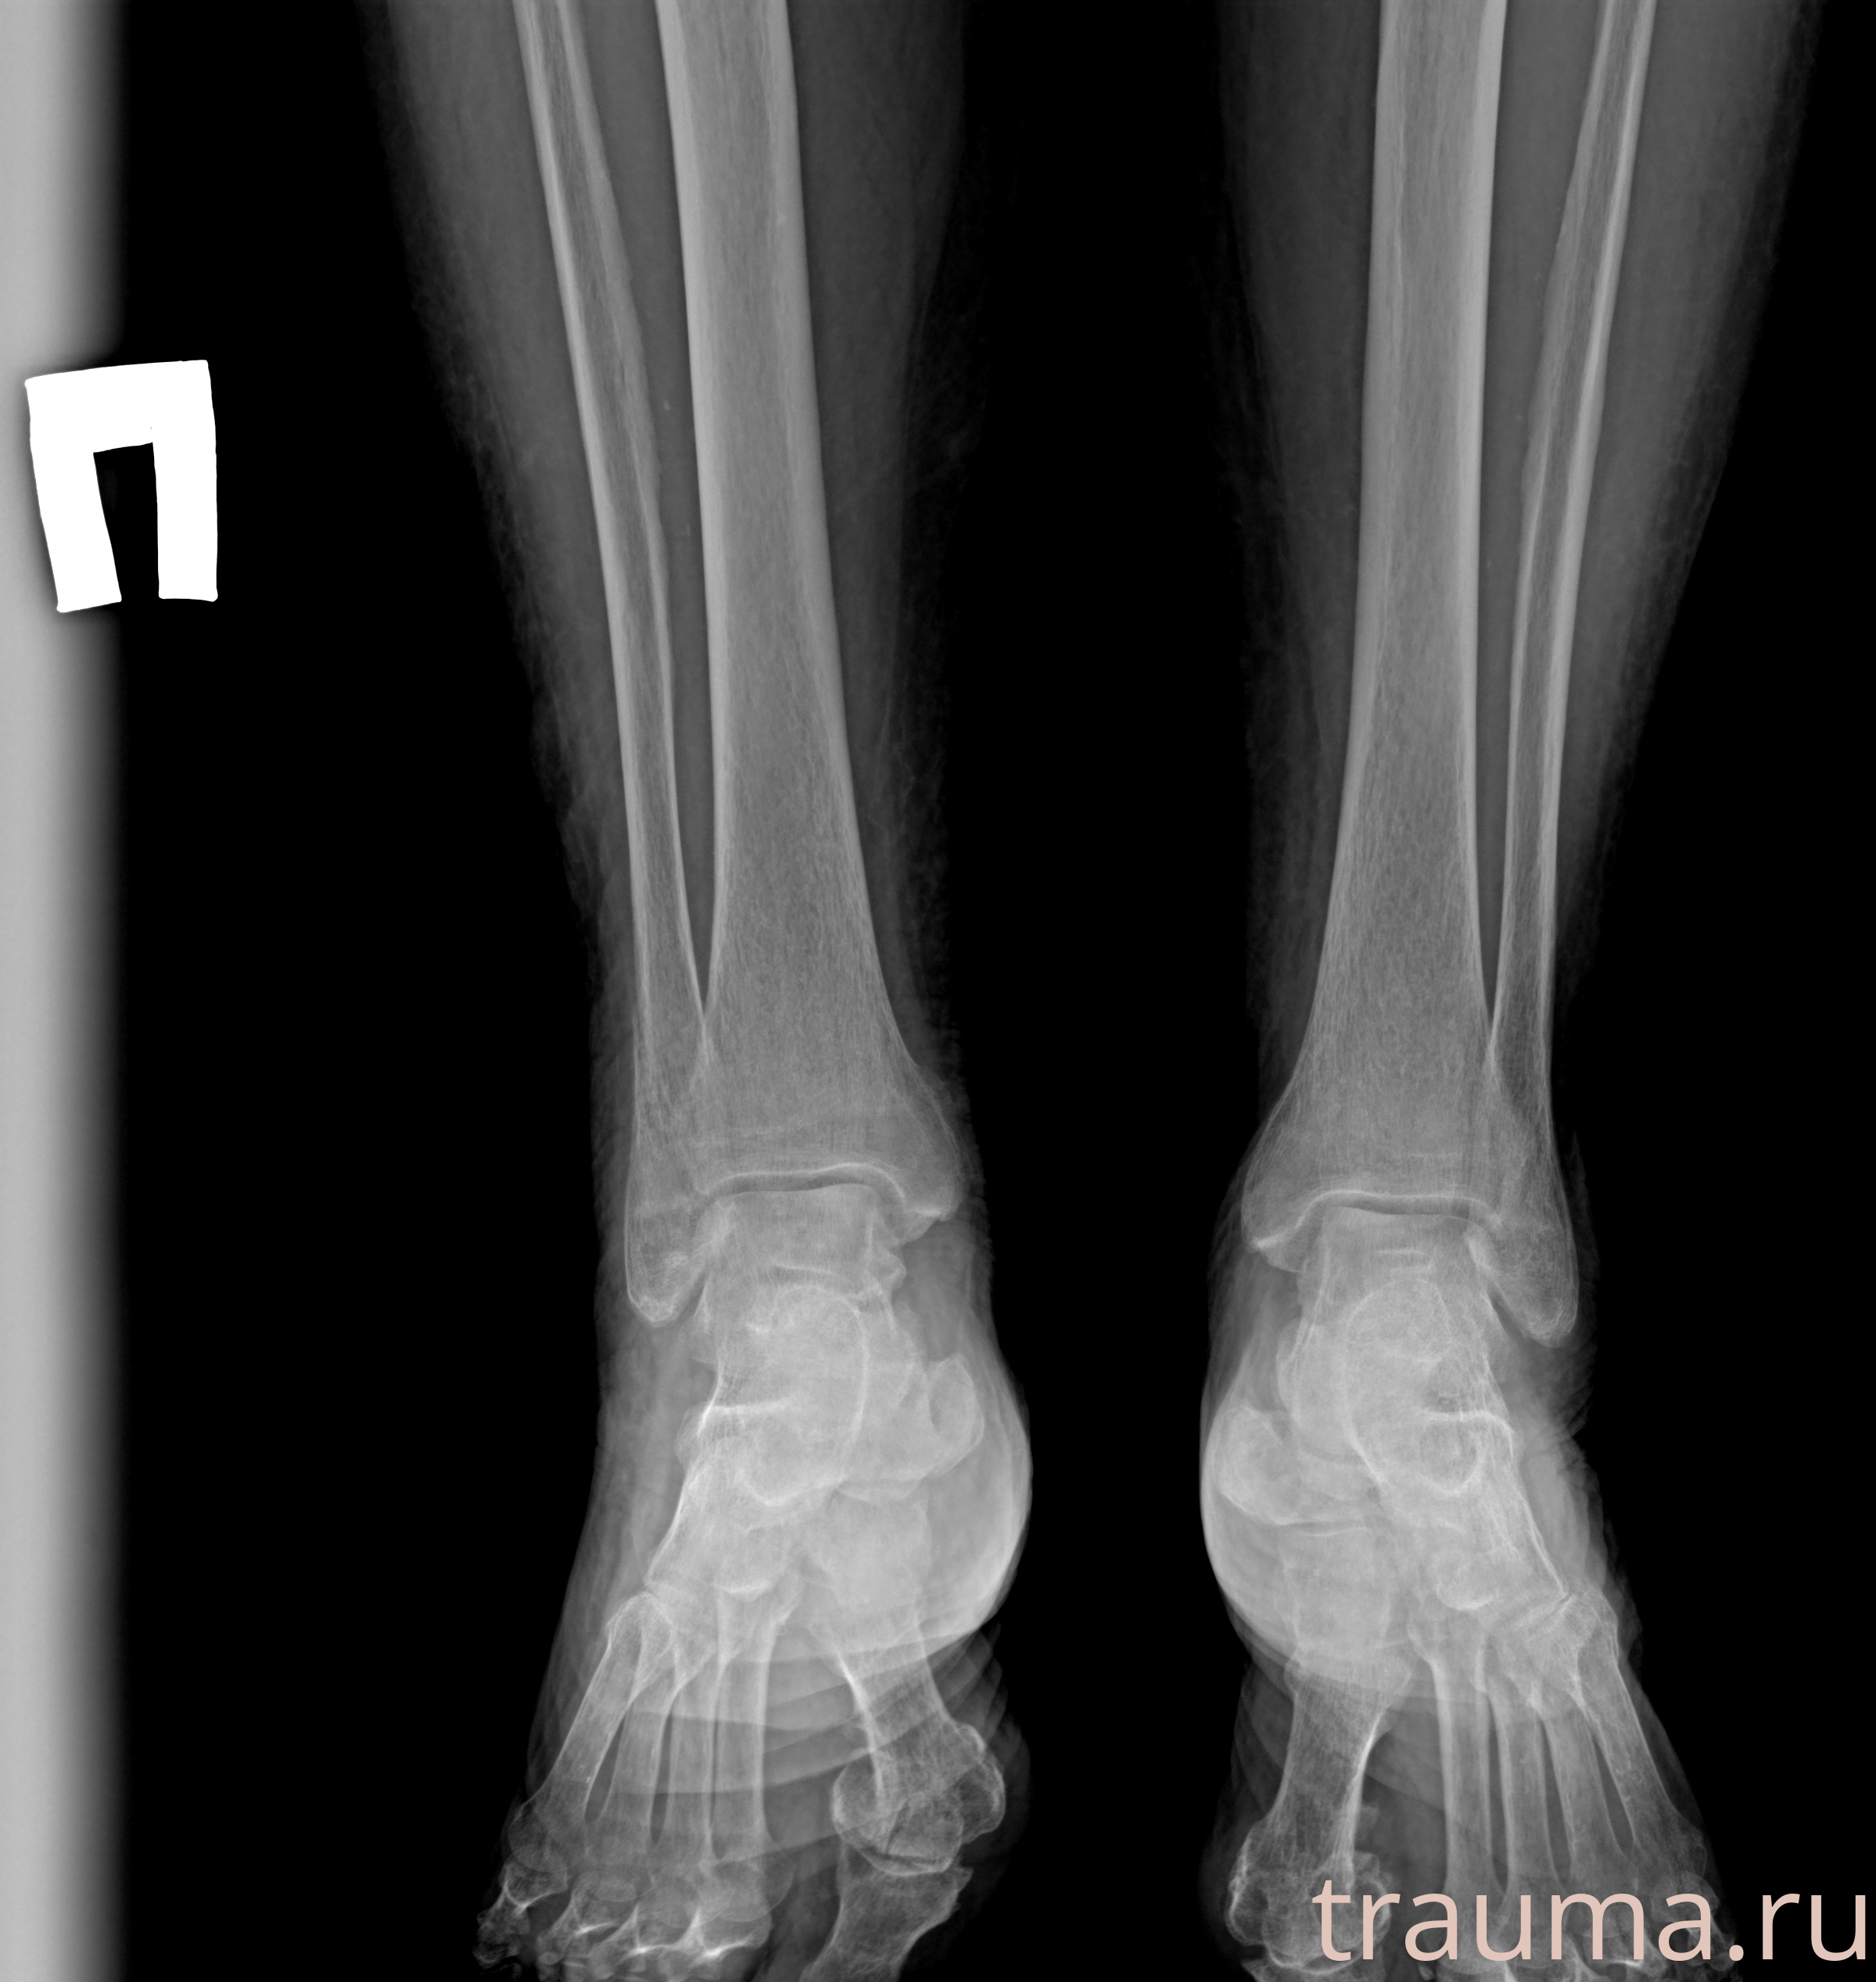

Рентгенограммы

Рентген на дому: по вашему адресу приезжает врач-рентгенолог, травматолог-ортопед с мобильным рентгеновским аппаратом, проводит диагностику травмы или заболевания, делает необходимые рентгенограммы, дает рекомендации по дальнейшему лечению. Получить качественные снимки в домашних условиях возможно благодаря уникальной методике, разработанной МосРентген Центром для института  Склифосовского